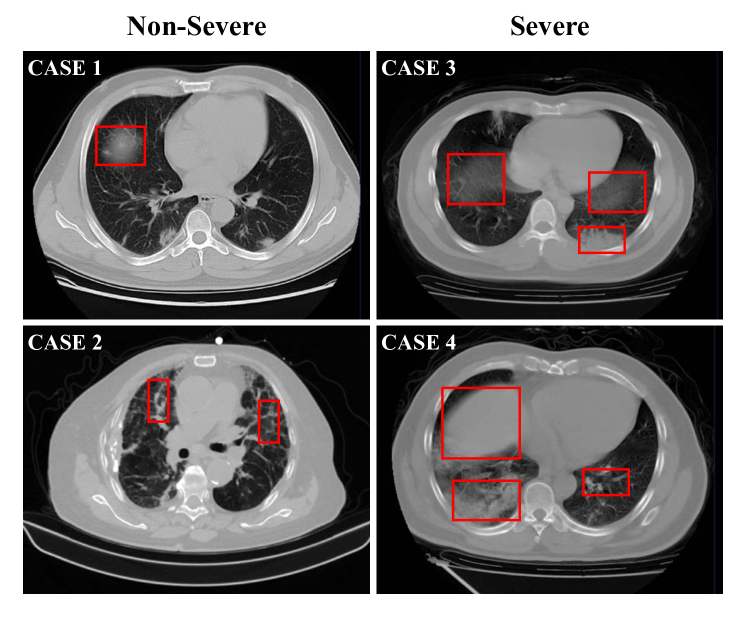

Figure 1: Typical cases of two non-severe (left) and two severe (right) patients with COVID-19, where infections often occur in small regions of the lungs in CT images. The similar imaging biomarkers (e.g., ground glass opacities, mosaic sign, air bronchogram and interlobular septal thickening) of both cases (denoted by red boxes) make the non-severe and severe images difficult to distinguish.

However, automatically assess the severity of COVID-19 in CT images is a very challenging task. First, infections caused by COVID-19 often occur in small regions of the lungs and are difficult to identify in CT images, as shown in Fig. 1. Second, imaging biomarkers of COVID-19 patients caused by an infection are similar in some severe and non-severe cases are similar, including ground-glass opacities (GGO), mosaic sign, air bronchogram, and interlobular septal thickening (Fig. 1). In addition, there are large inter-case variations in CT images of COVID-19 patients (Fig. 2), because these images are usually acquired by multiple imaging centers with different scanners and different scanning parameters.